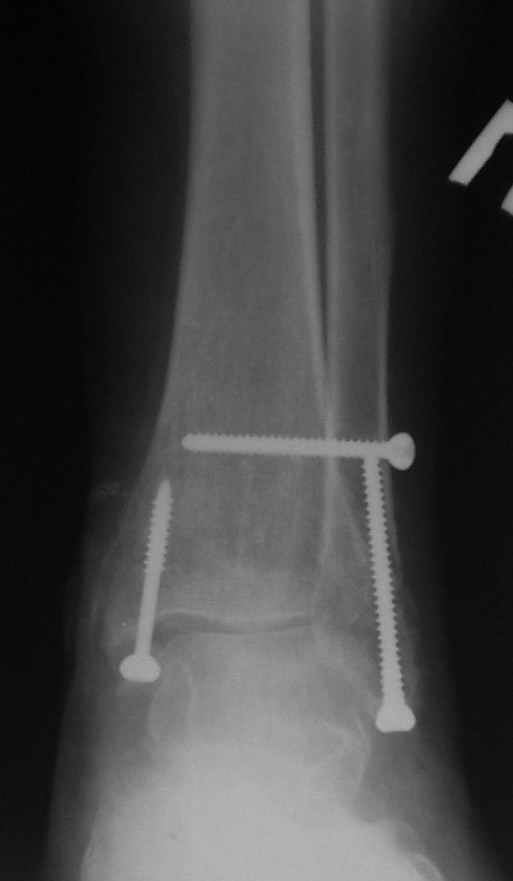

12 января прямой

12 января боковой

12 января трехчетвертной